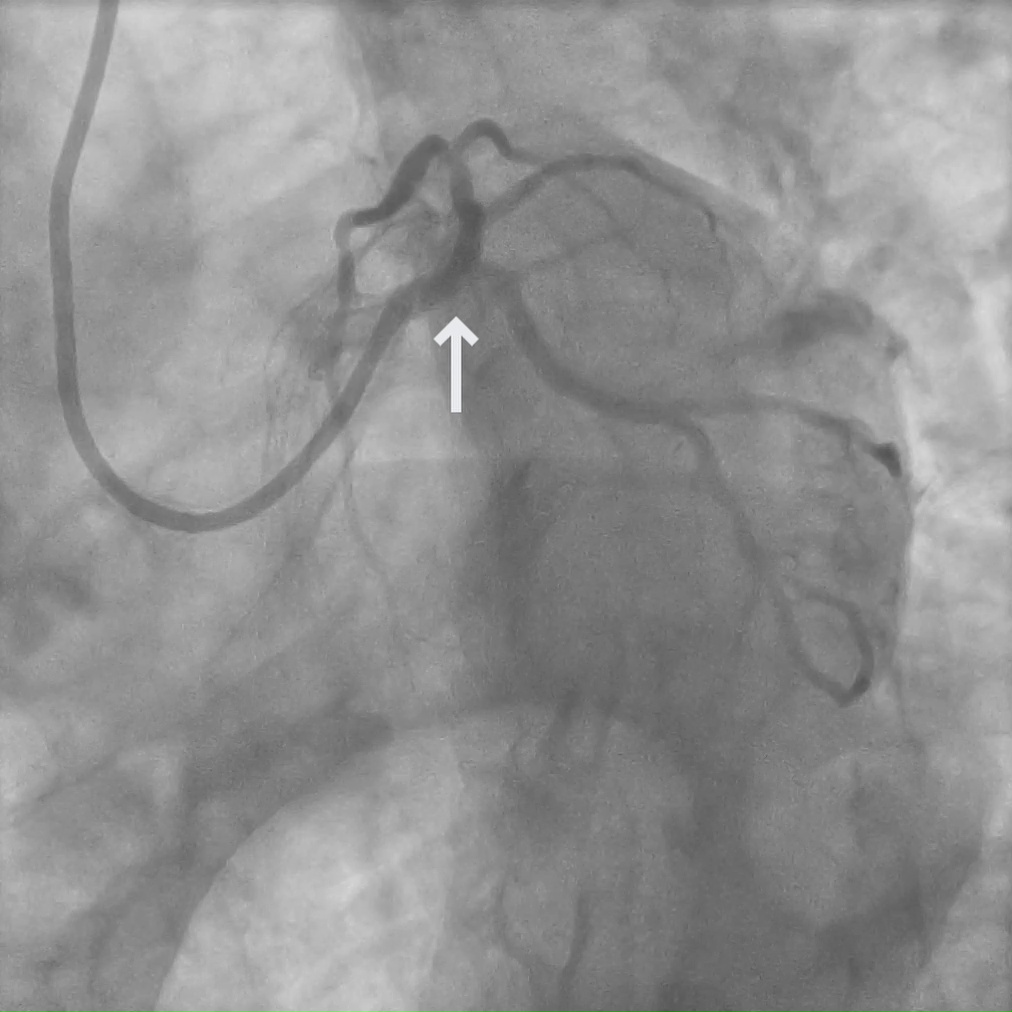

A 76-year-old male with nonobstructive CAD presents with severe chest pain and a syncopal episode.